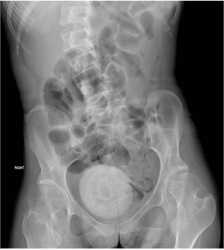

Doctors said she looked pale and lethargic. A CT scan was performed on her abdomen and pelvis, and images showed a large, round mass in her pelvic area.